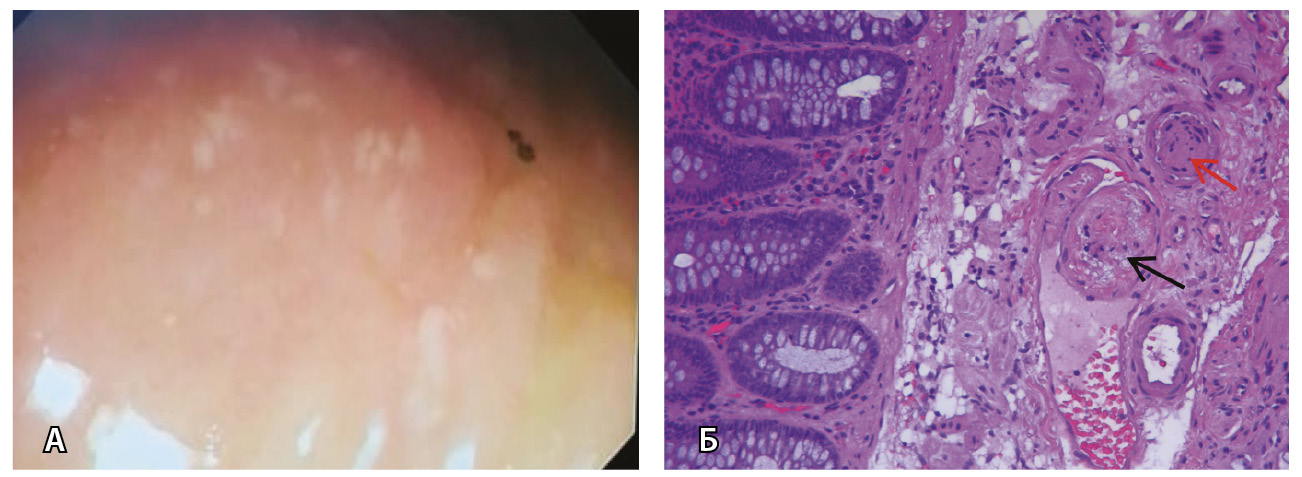

Рис. 4. Эрозии слизистой оболочки толстой кишки после инфекции SARS-CoV-2 у больной 38 лет: А – эрозии слизистой оболочки сигмовидной кишки с отсутствующим местами сосудистым рисунком; Б – мелкие эрозии на фоне сохраненного сосудистого рисунка в нисходящей ободочной кишке

Рис. 10. Поражение толстой кишки у больной 48 лет после перенесенной инфекции SARS-CoV-2: А – при илеоколоноскопии видны единичные эрозии слизистой оболочки толстой кишки; Б – по данным биопсии из подслизистого слоя толстой кишки обнаружены фибриновые тромбы в просветах вены (черная стрелка) и артерии мелкого калибра (красная стрелка) подслизистого слоя в отсутствие воспаления в собственной пластинке слизистой оболочки. Окраска гематоксилином и эозином; × 200

5. Fig. 4. Erosions of the colonic mucosa after the SARS-CoV-2 infection in a 38-year old patient: А, erosions of sigmoid mucosa, with areas of absent vascular structures; B, small erosions with preserved vascular structure in the descending colon

11. Fig. 10. Colon lesions in a 48-year old patient after the SARS-CoV-2 infection: А, at ileocolonoscopy, single erosions of the colonic mucosa; B, the biopsy sample from the colonic submucosa showed fibrin clots in the venules (black arrow) and small artery (red arrow) of the submucosal layer, with no signs of inflammation in the lamina propria. Hematoxylin eosin stain; × 200